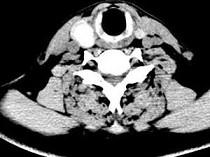

问题 男,43岁,右颈部扪及一包块,CT如图所示,应诊断为 ( )

选项 A、甲状腺原发淋巴瘤 B、甲状腺转移癌 C、甲状腺腺癌 D、结节性甲状腺肿 E、甲状腺腺瘤

答案 E